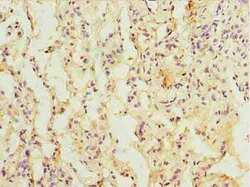

Immunohistochemistry

PA5-113237 IHC

Full details

Method: